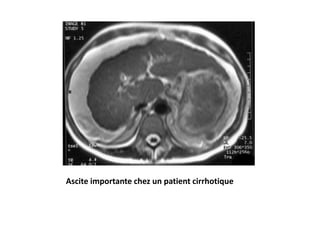

Ascite importante chez un patient cirrhotique

Ascite importante chezun patient cirrhotique